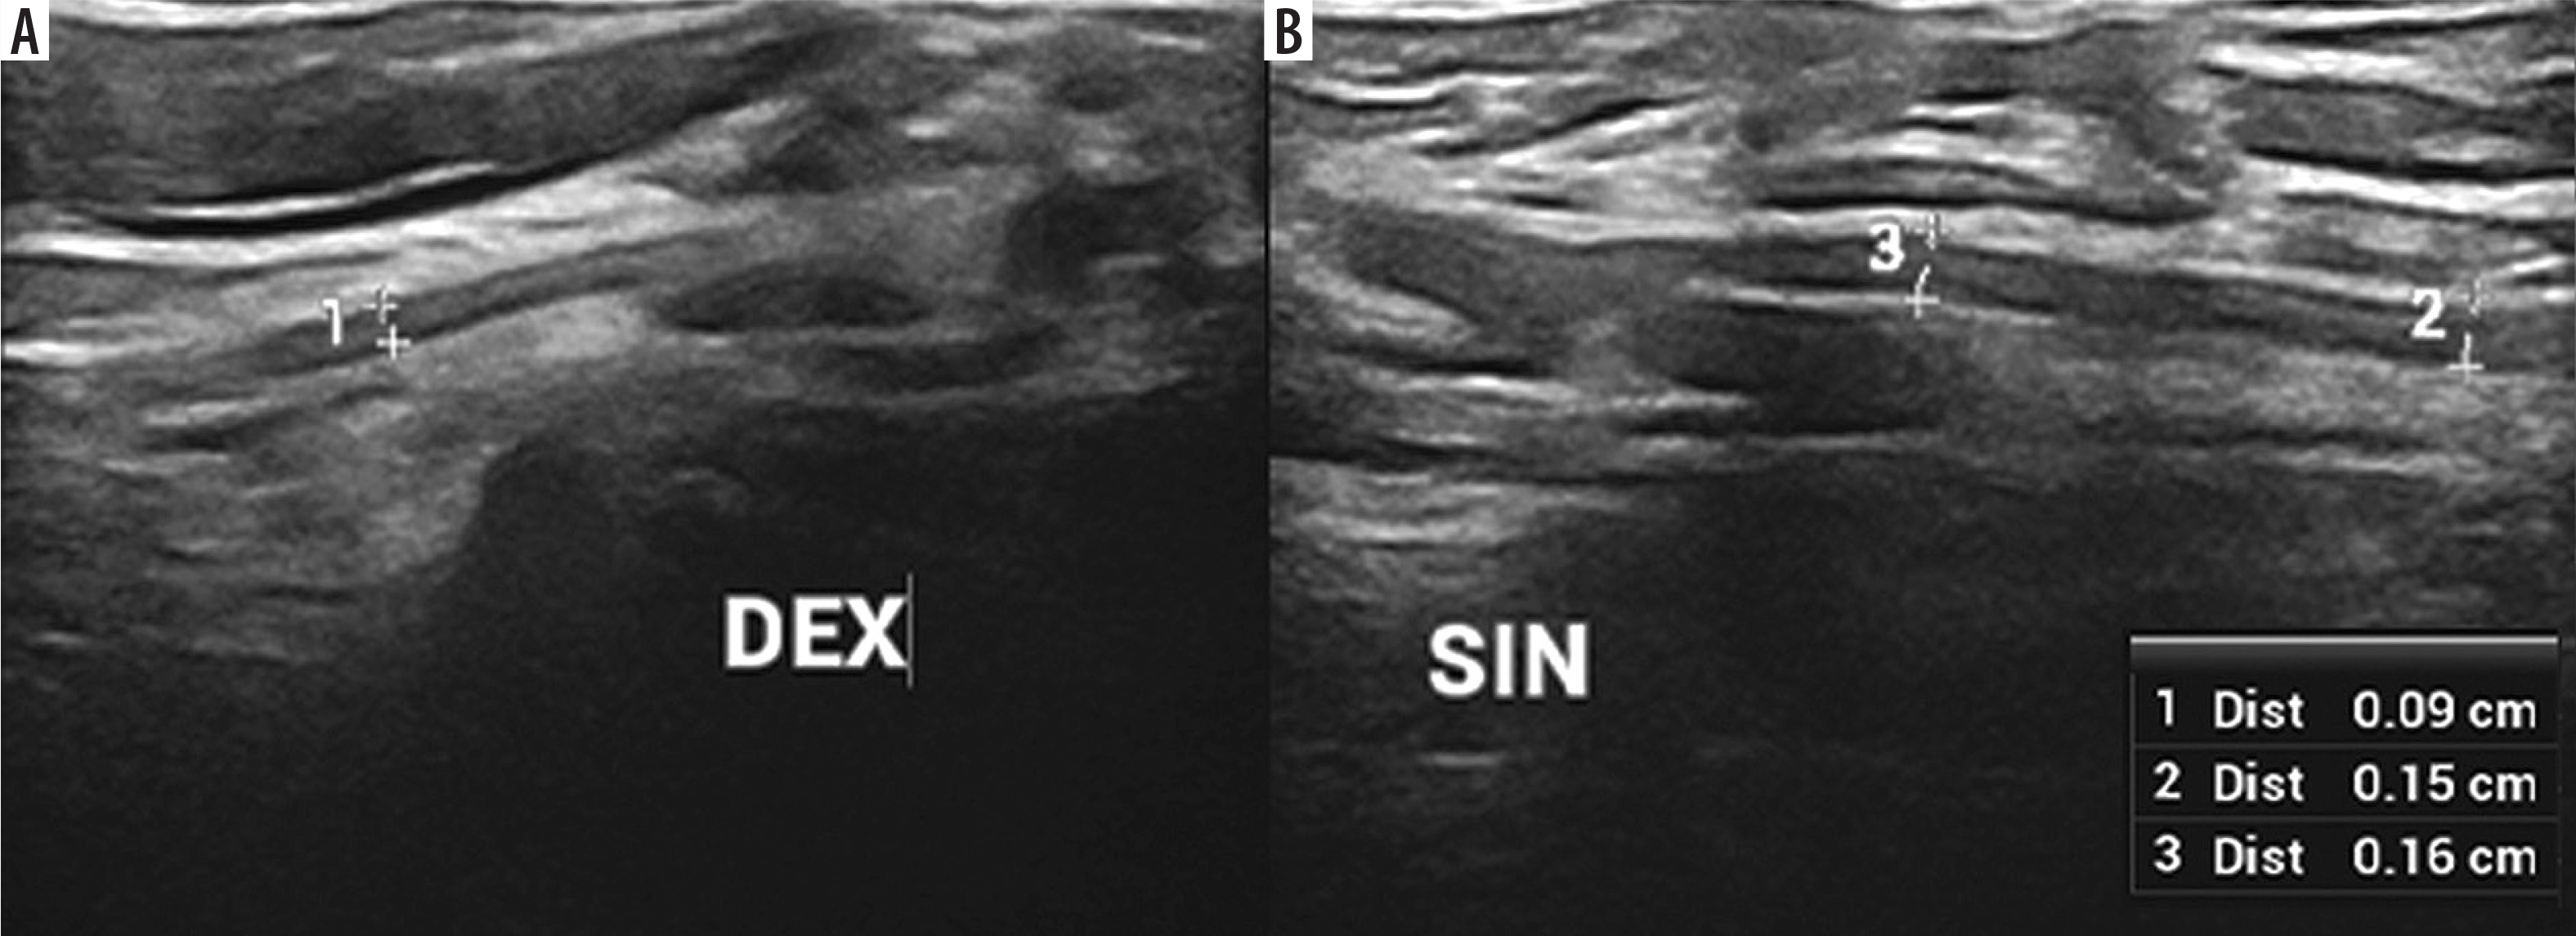

Figure 7

High-resolution ultrasound (HRUS) image of the suprascapular nerve (DEX – asymptomatic side, SIN – symptomatic side) with measurements in brachial neuritis due to neuroborreliosis. Side-by-side comparison. Images obtained by author with a 5-20 MHz linear probe of the Mindray Resona I9